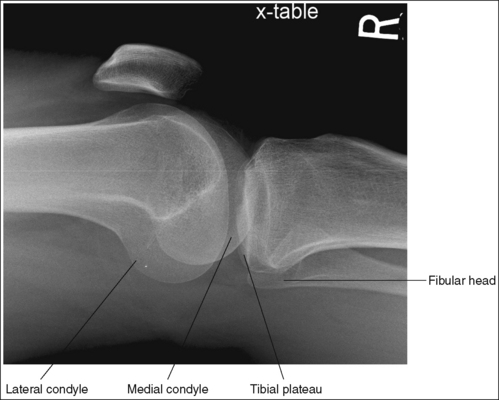

• Supine (cross-table) lateromedial knee projection. When a lateral knee projection is taken using a lateromedial projection, with a horizontal central ray, the cephalad central ray angulation described above is not required, as long as the patient's femoral inclination is not reduced or increased by the distal femur being shifted too laterally or medially, respectively. Images 70 and 71 are cross-table lateral knee projections that demonstrate a femoral condyle within the knee joint space because of poor femoral positioning. Image 70 demonstrates the lateral condyle in the joint space and image 71 demonstrates the medial condyle. When such images are produced, view how far the fibular head is positioned from the tibial plateau. When the distal surfaces of the femoral condyles are accurately superimposed, the fibular head will be positioned about 0.5 inch (1.25 cm) from the tibial plateau. If the central ray (CR) is rotated distally or the leg adducted (moved too medially) for a lateromedial projection of the knee, the lateral condyle will be projected distal to the medial condyle and the fibular head will move farther than 0.5 inch (1.25 cm) from the tibial plateau (see Image 70). If the CR is rotated proximally or the leg abducted (moved too laterally) for a lateromedial projection of the knee, the lateral condyle will be projected proximal to the medial condyle and the fibular head will move closer than 0.5 inch (1.25 cm) from the tibial plateau (see Image 71).